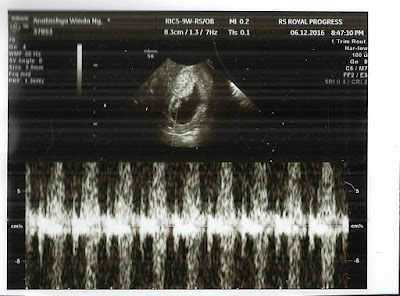

Hai kamu yang masih seukuran buah anggur. Makasih ya udah bertahan sampai saat ini. Semoga kamu sehat-sehat terus dan tumbuh kuat sampai kita ketemu nanti :) I'm 9 weeks pregnant now. Rasanya hepi, bersyukur dan yang pasti gak nyangka. Apalagi waktu itu keadaannya aku lagi cukup stres karena banyak hal. Ditambah kesotoyan pas ngitung tanggal subur yang ujung-ujungnya ternyata salah lol. Tau salahnya itu setelah temen kasih tau untuk download aplikasi yang bisa ngitung masa subur gitu-gitu. Sampai akhirnya di suatu sore tanggal 13 November 2016, si "merah" itu datang juga. Bulan sebelumnya, aku haid di tanggal 15 dan biasanya aku punya siklus yang cukup teratur, kalaupun telat itu 2-3 hari aja. Pas tanggal 13 itu sebenernya masih kecepetan dua hari dan mikir mungkin karena lagi cape makanya dateng lebih cepet. Apa kebalik ya? Harusnya kan kalo lagi cape, datengnya malah lebih telat. Hmm biarin lah gak usah dipikirin hehe.. Jadi tanggal 13 itu aku bilang ke Kevin kalo...